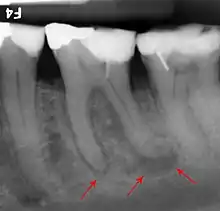

Apical abscess associated with roots of a lower molar.

Apical periodontitis is acute or chronic inflammation around the apex of a tooth caused by an immune response to bacteria within an infected pulp.[20] It does not occur because of pulp necrosis, meaning that a tooth that tests as if it's alive (vital) may cause apical periodontitis, and a pulp which has become non-vital due to a sterile, non-infectious processes (such as trauma) may not cause any apical periodontitis.[10]:225 Bacterial cytotoxins reach the region around the roots of the tooth via the apical foramina and lateral canals, causing vasodilation, sensitization of nerves, osteolysis (bone resorption) and potentially abscess or cyst formation.[10]:228

The periodontal ligament becomes inflamed and there may be pain when biting or tapping on the tooth. On an X-ray, bone resorption appears as a radiolucent area around the end of the root, although this does not manifest immediately.[10]:228 Acute apical periodontitis is characterized by well-localized, spontaneous, persistent, moderate to severe pain.[6]:125–135 The alveolar process may be tender to palpation over the roots. The tooth may be raised in the socket and feel more prominent than the adjacent teeth.[6]:125–135